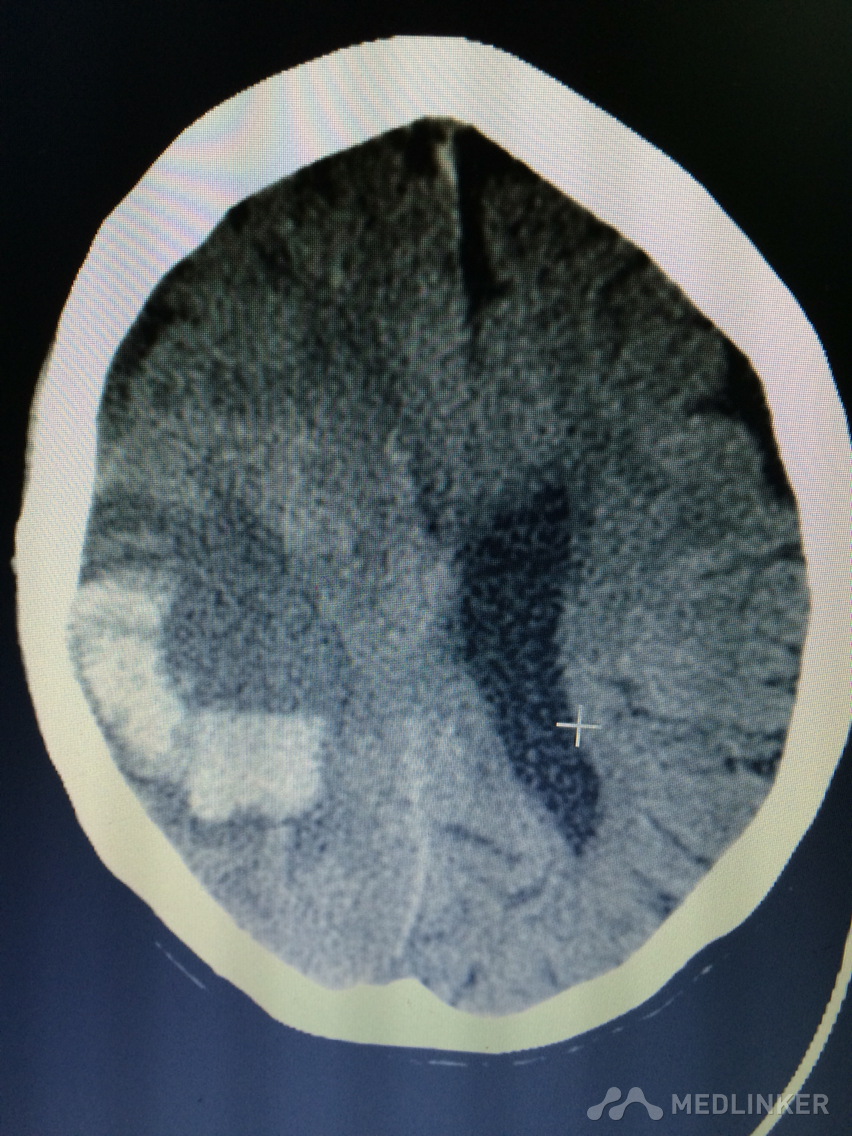

下面的CT考虑?

1天前,患者睡醒后出现反应迟钝,认知功能障碍,左侧肢体乏力。 既往无高血压病史,近期无外伤史。